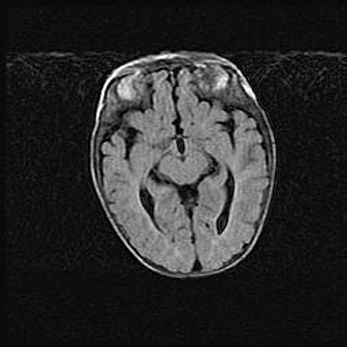

Церебральная ишемия II.

Возраст: 5 дней

Вес: 3400 г

Пол: женский

Окружность головы: 35 см

Срок гестации: 39 недель

Церебральная ишемия – это заболевание, характеризующееся недостаточностью (гипоксией) либо полным прекращением (аноксией) снабжения мозга кислородом по причине закупорки одного или нескольких сосудов. Это приводит к  что метаболическим расстройствам различной степени тяжести в тканях головного мозга, развитию коагуляционных некрозов и гибели нейронов.